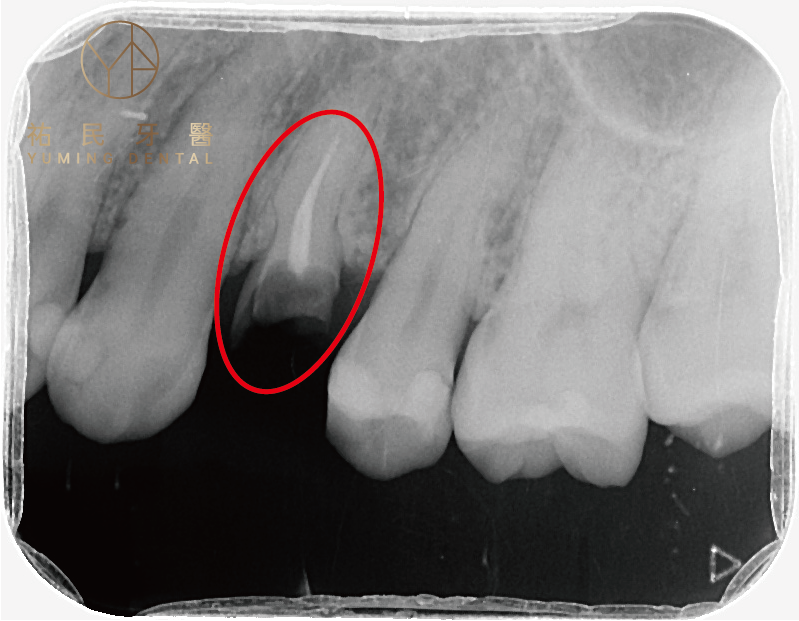

▲從X光片可以看出只剩殘留的牙根,牙根會很容易引起感染,所以殘留的牙根必須拔掉,才不會造成牙周問題。

(1) 只剩殘根

當牙齒斷到只剩下牙根,卡在牙齦內,幾乎與牙齦齊平,這時殘留的牙根容易造成細菌感染,甚至在牙根尖周圍形成囊腫或膿包,嚴重影響咬合功能和口腔健康。為了避免感染擴大,必須將這些殘留的牙根拔掉。